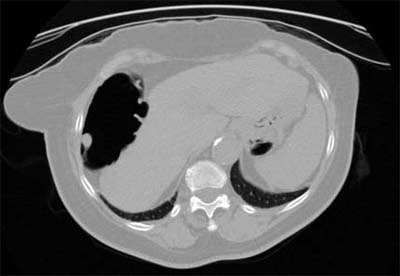

| Axial 2-D CT image showing a 12-mm pedunculated polyp in the hepatic flexure. Image courtesy of Dr. Abraham Dachman, University of Chicago. |